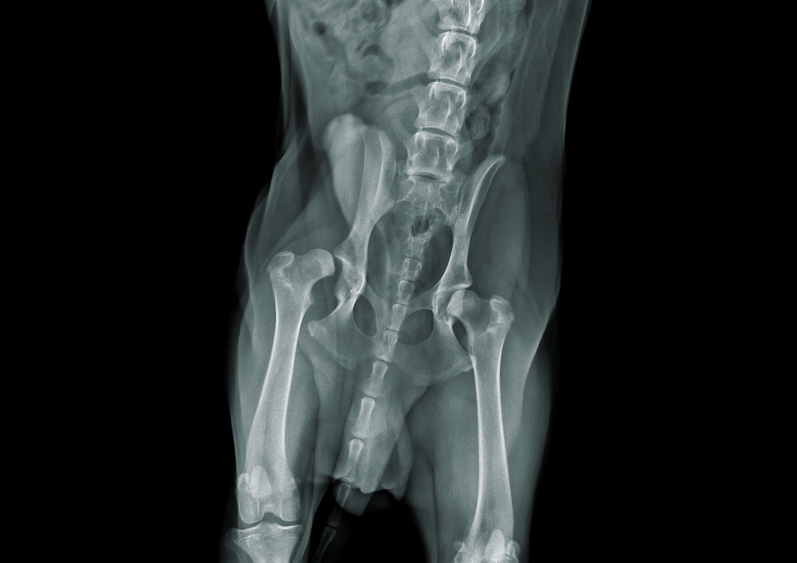

La radiographie produit une image fixe en utilisant des rayons X. Elle est idéale pour examiner les structures dures comme les os, les dents ou les structures aériques comme les poumons. Cette image instantanée est l’équivalent d’une photo, elle ne montre pas le mouvement ou le fonctionnement des organes.

Grâce à la radiographie :

- Fracture

- Pneumonie

- Pierres dans la vessie